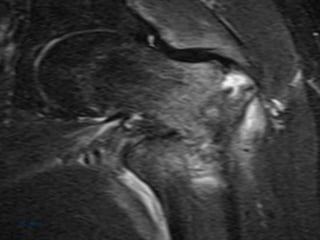

 Ressonância magnética

 Cintilografia com tecnécio

 Ressonância magnética Cintilografia com tecnécio 05/10/19